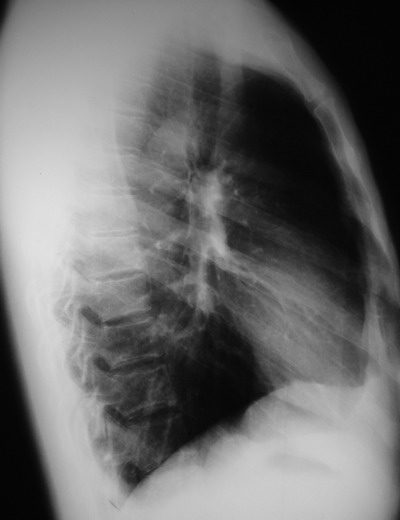

以下是引用余辉在2007-6-16 20:47:00的发言:[br]图像不边续,1左肺下叶膈后囊性病灶,与胃有密切联系,考虑局限性膈膨隆,不排除其他如脓肿等;2左膈肌脚增厚,其前方肝胃间隙内可见球形病灶,左肾上腺病变?进一步检查

以下是引用xulianj在2007-6-16 21:14:00的发言:[br]左膈肌脚增厚,支持膈肌角病变。

以下是引用卜一在2007-6-17 4:50:00的发言:[br]左膈肌脚增厚,支持膈肌角病变。